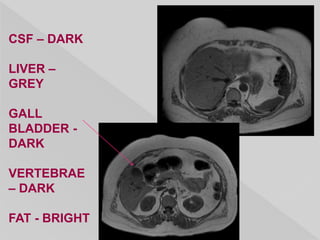

CSF – DARK

LIVER –

GREY

GALL

BLADDER -

DARK

VERTEBRAE

– DARK

FAT - BRIGHT

CSF – DARK LIVER– GREY GALL BLADDER - DARK VERTEBRAE – DARK FAT - BRIGHT